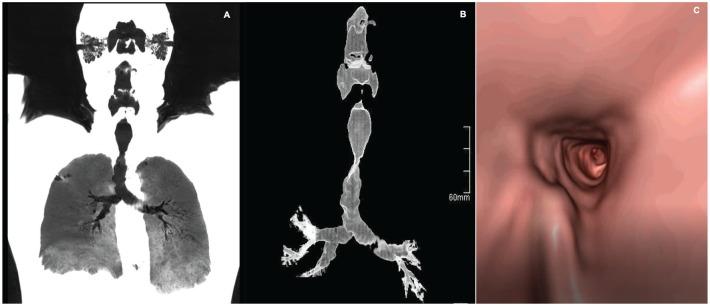

Tracheobronchopathia osteochondroplastica (TO) is a rare idiopathic and benign disease that is often underdiagnosed. TO is characterized by multiple submucosal cartilaginous and osseous tracheobronchial nodules that spare the posterior wall. It usually affects the elderly, developing when the person is around 60 years old without gender preference and has a reported incidence of 0.11%. TO can be symptomatic and should be considered in patients with chronic cough, dyspnea, and recurrent pulmonary infections. Diagnosis is usually incidental by computed tomography or bronchoscopy, the latter being the gold standard diagnostic test for TO. Many thoracic imagers are not well acquainted with TO; thus, these patients are often underdiagnosed or misdiagnosed. We came across 5 patients in our institution who were incidentally diagnosed with TO, inspiring us to review the available literature on this disease. A total of 33 patients diagnosed with TO between 2009 and 2019 were identified by our retrospective review. Clinical and imaging data were collected on these patients. We also included the clinical, radiological, and endoscopic data of our 5 cases. TO should be considered in patients with chronic cough, dyspnea, and recurrent pulmonary infections. Our experience is that both computed tomography and bronchoscopy can be used to make a reliable diagnosis. It is crucial for physicians, especially radiologists and pulmonologists, to be aware of the existence of TO in order to ensure proper diagnosis.

气管支气管软骨骨肥厚症(TO)是一种罕见的特发性良性疾病,常被漏诊。TO 的特征是多个气管支气管黏膜下软骨和骨性结节,不侵犯后壁。它通常发生在老年人身上,发病年龄在 60 岁左右,无性别偏好,发病率为 0.11%。TO 可能有症状,应考虑患有慢性咳嗽、呼吸困难和反复肺部感染的患者。诊断通常通过计算机断层扫描或支气管镜检查偶然发现,后者是 TO 的金标准诊断测试。许多胸科成像医生对 TO 并不熟悉;因此,这些患者经常被漏诊或误诊。我们在医院偶然诊断出 5 例 TO 患者,这激发了我们对这种疾病的现有文献进行回顾。通过回顾性分析,共确定了 2009 年至 2019 年间 33 例被诊断为 TO 的患者。收集了这些患者的临床和影像学数据。我们还包括了我们 5 例病例的临床、放射学和内镜数据。对于患有慢性咳嗽、呼吸困难和反复肺部感染的患者,应考虑 TO。我们的经验是,计算机断层扫描和支气管镜检查均可用于做出可靠的诊断。医生,尤其是放射科医生和肺病学家,了解 TO 的存在对于确保正确诊断至关重要。